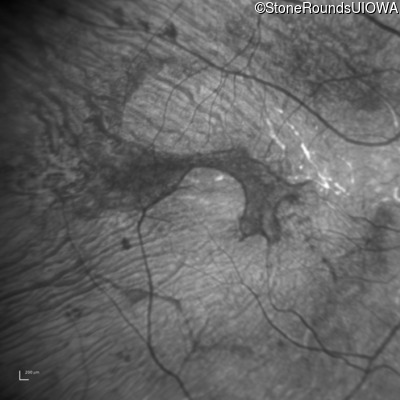

Infrared Fundus Photograph - Left - 20/60

Exemplar